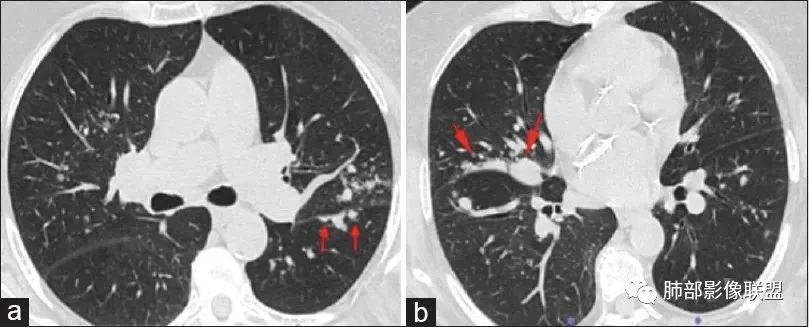

原发性肺淋巴瘤是一种影响肺部的单克隆淋巴样增生,患者在最初诊断后至少 3个月内没有可检测到的胸外淋巴瘤。原发性肺淋巴瘤很少见,占所有原发性肺肿瘤的 0.5%。原发性肺部受累的淋巴组织增生性疾病包括黏膜相关淋巴组织起源的结外边缘区淋巴瘤(MALT)、弥漫性大 B 细胞淋巴瘤(DLBCL)和淋巴瘤样肉芽肿(LYG)。MALT淋巴瘤是一种低级别B淋巴细胞淋巴瘤,由具有局灶性浆细胞样特征的单调小淋巴细胞组成。它们由沿远端支气管和细支气管分布的上皮下淋巴滤泡组成。肿瘤可能有许多关联,其中包括:干燥综合征、异常丙种球蛋白血症、淀粉样蛋白沉积、胶原血管病、幽门螺杆菌感染和艾滋病等。其影像学表现复杂多变,通常表现为孤立的、界限清楚的软组织肿块。不太常见的成像特征包括:多个单侧或双侧结节沿支气管血管束和小叶间隔弥漫性浸润、广泛的肺叶浸润、模拟实变(肺炎)、伴有空气支气管征或磨玻璃样改变。这些由外淋巴结节、间隔和支气管血管周围增厚组成的间质模式看起来与癌性淋巴管炎或结节病所见的相同。

中央淋巴道分布(支气管血管束分布)外周淋巴道分布(小叶间隔和胸膜下分布)

肺淋巴瘤表现多种多样。可表现为多发小结节!